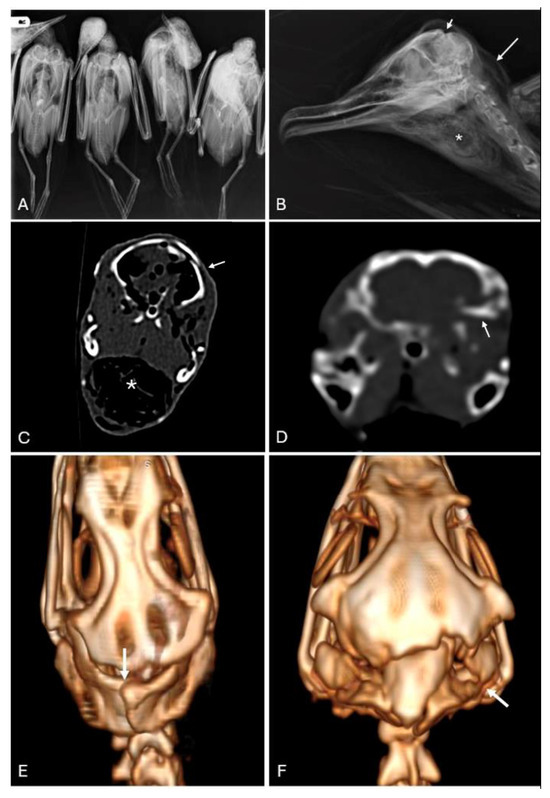

This study characterizes the pathological findings in Atlantic Cory’s shearwater (Calonectris borealis) chicks from the Canary Islands associated with illegal hunting cases. A retrospective analysis of necropsy archives, including imaging techniques (X-rays and computed tomography) and histopathological examinations, was conducted on [...] Read more.

This study characterizes the pathological findings in Atlantic Cory’s shearwater (Calonectris borealis) chicks from the Canary Islands associated with illegal hunting cases. A retrospective analysis of necropsy archives, including imaging techniques (X-rays and computed tomography) and histopathological examinations, was conducted on twenty juvenile shearwaters. The study revealed significant cranioencephalic trauma as the primary cause of death in both poaching events. Differences in the methods used by the perpetrators were noted, with variations in skull fractures and associated injuries. These findings highlight the importance of understanding local hunting techniques and sociocultural factors in forensic investigations. Diagnostic imaging, standardized necropsy, and histopathology are essential tools for the forensic investigation of illegal hunting in veterinary sciences. Full article